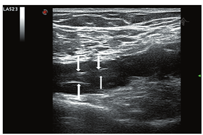

患者男,46岁,已婚。3个月前无明显诱因出现左下肢发凉、疼痛、麻木,间歇性跛行,跛行距离约100 m,休息后可缓解。无明显肿胀,皮肤无溃烂及色素沉着。既往体健,无糖尿病、高血压、脑血管病及外伤史。无饮酒、吸毒及毒物接触史。吸烟25年,平均20支/d,未戒烟。头颅CT、胸部平片、肺功能测定、血清学检测及心电图均未见异常。一般情况好,生命体征未见异常。查体:左下肢皮肤苍白,尤以膝关节以下为著,左小腿及左足皮温低,左侧股动脉搏动良好,左侧腘动脉及左侧足背动脉搏动未触及,左下肢末梢血运及感觉差。右下肢未见明显异常。生理反射存在,病理反射未引出。超声显示:左侧腘动脉走行处见长约45 mm的不规则异常回声区,挤压无明显形变,最宽处直径约12 mm,管壁不规则增厚,回声较低,其内可见不规则强回声带及不连续内膜较强回声(图1)。彩色多普勒血流显像(CDFI)示腘动脉不规则长条状血流信号,远端动脉呈小慢波。注入SonoVue造影剂后测得最窄处血流信号宽度1 mm,低回声的增厚的管壁内未见明确造影剂信号回声(图2)。超声提示:左侧腘窝所见不排除腘动脉外膜囊性病变,局部管腔不完全闭塞,建议进一步检查。随后行下肢血管CTA示左侧腘动脉管腔内见低密度充盈缺损,管腔变窄,最窄处狭窄程度约80%,狭窄长度约17.1 mm,诊断意见:左侧腘动脉低密度影,考虑血栓形成,管腔重度狭窄(图3)。患者择期手术。术中所见:左侧腘窝处可见一大小约4 cm×4 cm囊性包块,将腘动脉紧密包绕,包块近端腘动脉搏动良好,远端未见明显搏动(图4);打开囊肿外膜,可见其内充满无色透明"冻胶状"物,量约20 ml,完全清除囊肿内容物后,钝锐性结合,将囊肿从腘动脉上完整分离并切除。病理所见:破碎囊样组织,面积2 cm×1.5 cm,一侧灰白尚光滑,囊壁厚0.2~0.3 cm,另见胶冻样物。符合血管外膜囊性改变。